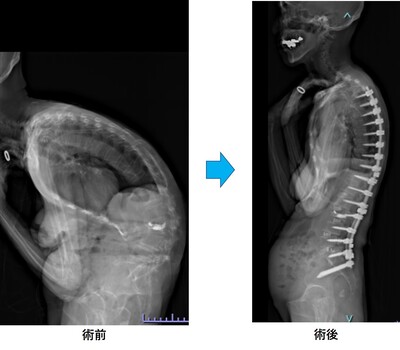

思春期特発性側弯症の全脊椎レントゲンで背骨が大きくSの字に曲がっています。最も曲がっている箇所は80°で、高度側弯に分類されます。後方からの脊柱側弯矯正術で真っ直ぐになっています。

また、側弯の患者さんは一般的にフラットバックと言って背骨の生理的後弯(背中の丸み)が失われています。この症例も胸椎後弯角は5°で典型的なフラットバックを呈しています(正常は20°~30°程度です)。この影響は頸椎の形態にも影響を及ぼし、この症例も頸椎が既に後弯(正常は前弯)しています。(黄色矢印)

ストレートネックという頸椎の前弯が消失して頸部の愁訴が出現する病態は広く知られていますが、更に変形が進行した頸椎と考えて下さい。

以前はこのフラットバック(生理的胸椎後弯の消失)を治すことは困難でしたが、当院では手術方法の様々な工夫により生理的胸椎後弯の復元を行っております。この症例は術後に胸椎後弯角が26°と改善しており、生理的な胸椎後弯が形成されています。さらに頸椎後弯にも良い影響を及ぼし、術後は頸椎前弯化が得られつつあるのが分かります。(黄色矢印)

他、側弯変形は必ず大なり小なりの回旋変形を伴います。脊柱の回旋変形は胸郭(肋骨)の回旋につながり、これにより側弯の患者さんは背中の片方が出っ張っています(多くは右)。リブハンプと言いますが、脊柱変形矯正によりこの回旋変形も改善します。この症例も術前に肋骨がかなり隆起していますが、術後にこの隆起がかなり減じているのが分かります。(赤矢印)

思春期特発性側弯症が高度に進行した症例です。最大側弯角度は113°であり、100°を超える側弯の手術は一般的に神経合併症が危惧されます。神経合併症を極力防ぐため、また侵襲を低減する目的で、同じ入院期間に2回に分けて段階的に矯正手術を行いました。1回目に最も側弯の強い箇所に対して側方から椎体間解離を行い、2回目に後方から全体のバランスが良くなるように慎重に矯正固定術を施行しています。

神経合併症はなく、術後の最大側弯角度は15°に改善(矯正率:87%)、背中の大きなコブも無くなっているのが分かります(赤矢印)。神経合併症が発生しないように慎重に手術を行うのは当然ですが、側弯を治すだけでなく横から見た姿勢を治すことにも留意しています。